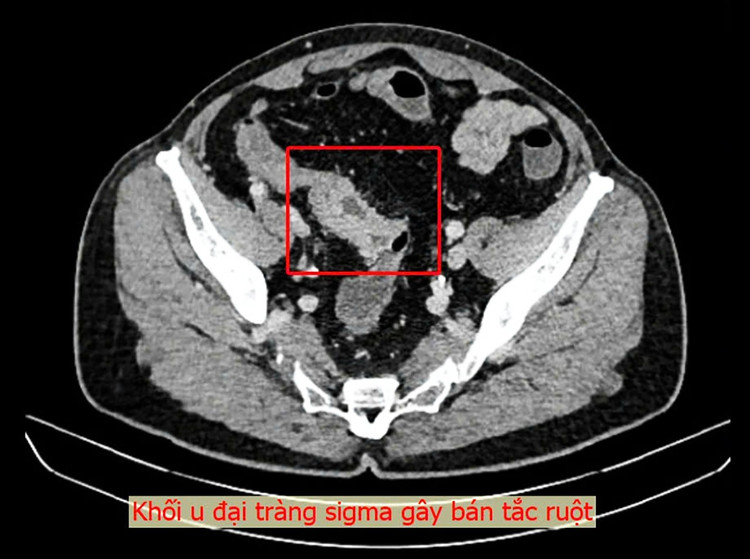

Một ca phẫu thuật nội soi thành công đã được thực hiện tại Bệnh viện Đa khoa Thủ Đức để điều trị cho nam bệnh nhân Việt kiều 73 tuổi bị bán tắc ruột do khối u đại tràng sigma.

Trong thời gian về Việt Nam, bệnh nhân đã đến khám tại Bệnh viện Đa khoa Thủ Đức. Qua nội soi đại tràng, các bác sĩ phát hiện một khối u lớn tại vị trí sigma-trực tràng, chiếm trọn lòng trực tràng, với đặc điểm mô bở và dễ chảy máu. Sau khi đánh giá toàn diện và xét nghiệm cần thiết, ê-kíp bác sĩ xác định đây là khối u ác tính và cần phẫu thuật gấp.

Ca phẫu thuật kéo dài 2 giờ 40 phút, thực hiện cắt bỏ đoạn đại trực tràng chứa u và nạo hạch D2. Kết quả giải phẫu bệnh sau mổ xác nhận đây là carcinôm tuyến đại tràng grade 2, đã xâm nhiễm đến cơ và lớp mỡ dưới thanh mạc.